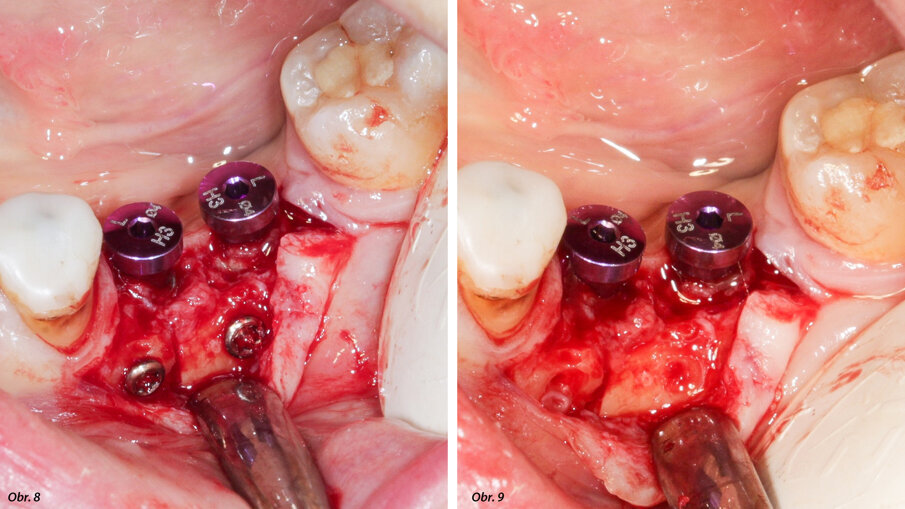

Na implantáty byly umístěny vhojovací válečky. Osteosyntetické šroubky byly odstraněny.

Měli jsme tři alternativní možnosti postupu: štěp kostního bloku z ramene dolní čelisti, segmentální osteotomii nebo radikulární štěp s vědomím, že zub 46 nebude vzhledem k jeho poškození možné zachránit. Zvolili jsme třetí možnost, protože umožňovala současné zavedení implantátu a rekonstrukci kosti. Byl odklopen rozsáhlý lalok, aby mohl být posouzen defekt kosti a uzavřen augmentovaný hřeben. Jako obvykle byly zavedeny dva implantáty, navzdory malé tloušťce reziduální kosti ve vestibulární oblasti plánovaných pozic pro implantáty (obr. 5). Kořeny zubu 46 byly atraumaticky extrahovány (separace kořenů byla provedena pomocí piezochirurgie) a připraveny podle výše uvedeného popisu. Kořeny byly vytvarovány tak, aby odpovídaly defektu a v oblasti transplantace byly zajištěny pomocí osteosyntetických šroubků (obr. 6). Lalok byl mobilizován a natažen tak, aby došlo k uzavření oblasti „end to end“ bez tahu, a k sešití bylo použito rychle vstřebatelné splétané vlákno č. 4/0 (obr. 7). Čtyři měsíce po augmentaci kosti a zavedení implantátu byly na implantáty umístěny vhojovací válečky a odstraněny osteosyntetické šroubky (obr. 8, 9). Během zákroku byl čas provést vizuální kontrolu toho, zda byla ankylóza radikulárních štěpů úspěšná a zda jsou štěpy zdravé. Nakonec bylo provedeno vyšetření pomocí CBCT. Náhradu nasadil náš kolega o několik týdnů později, jakmile byly zhojeny měkké tkáně.